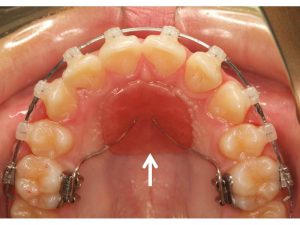

治療前。上顎の前歯の突出の改善を主訴に来院。上顎前歯の前方への突出が著しい。また下顎の前歯が上顎の歯茎を噛んでおり、過蓋咬合(ディープバイト)を呈している。上顎前歯の後方移動と過蓋咬合の改善が必要な症例。臼歯部の上下の咬合関係は完全な2級咬合(下顎遠心咬合)であるため、上顎の左右の第一小臼歯だけを抜歯する計画とした。

矯正治療後。上顎の小臼歯を抜歯したスペースを利用することで、上顎前歯が内側にきれいに並んでいることが分かる。過蓋咬合も改善し、個性正常咬合を確立した。上下の歯の数が異なる変則抜歯のケースでは、抜歯本数を最少に出来るものの、下顎第二大臼歯(一番奥の歯)は噛み合わせにあまり参加できない欠点もある。治療計画は、総合的に最善な結果が得られるよう立案し提案することが重要。